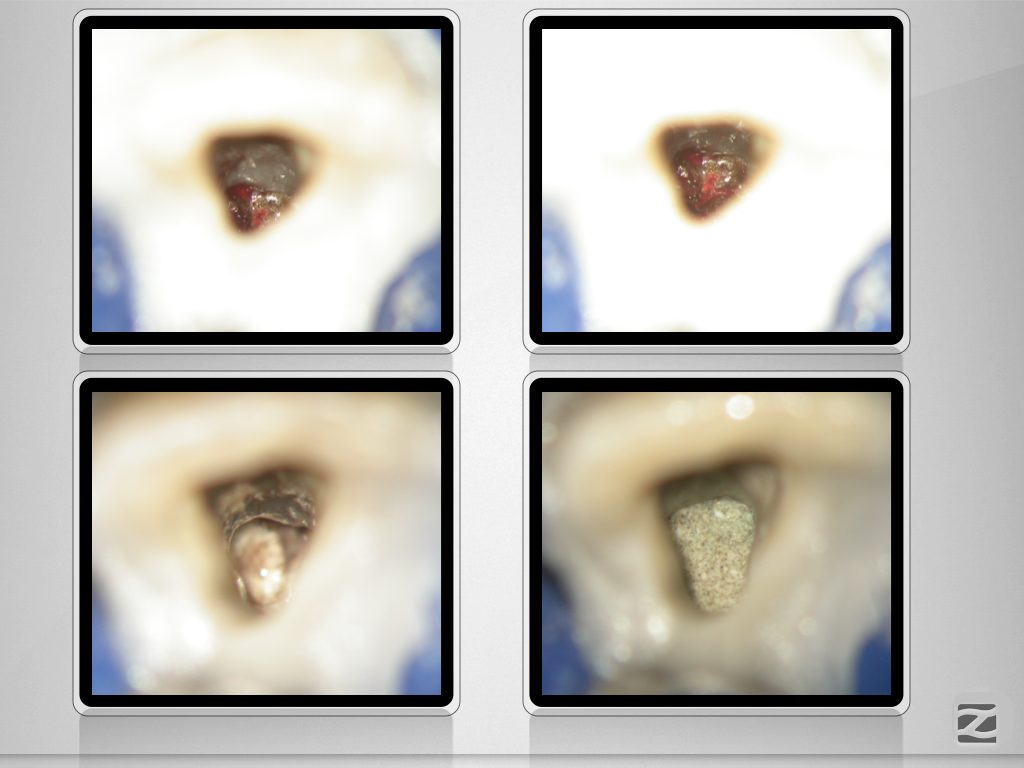

21D.012

Traumspätfolge